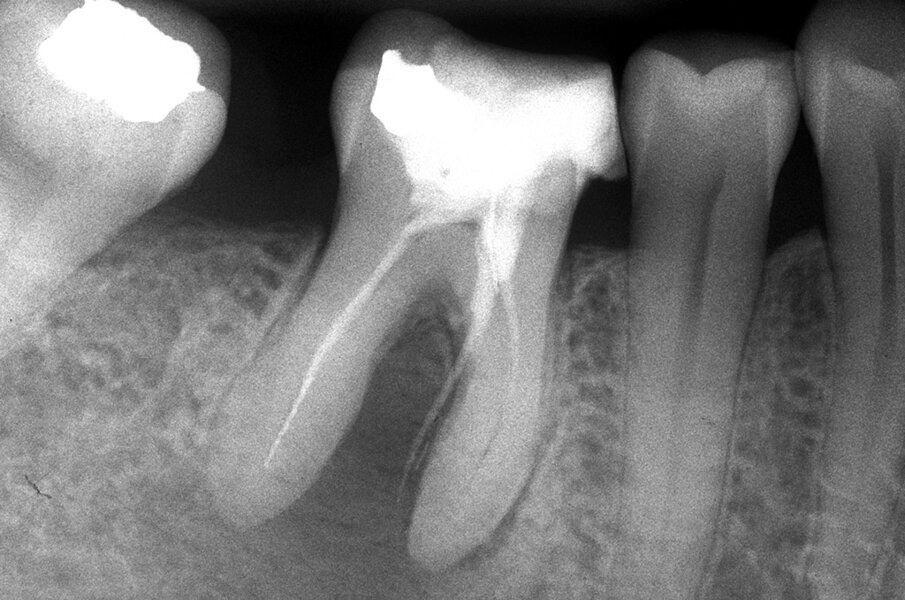

Queste perforazioni possono avvenire nel corso della strumentazione di canali curvi, per l’esecuzione del cosiddetto “trasporto esterno” del forame apicale. Una volta eseguita la perforazione, se l’operatore riesce a ritrovare e preparare il canale originale (con l’utilizzo di strumenti sottili e precurvati, molta irrigazione e soprattutto molta pazienza), il danno provocato dalla perforazione sarà minimo in quanto, soprattutto se la perforazione è piccola, si comporterà come un piccolo canale laterale che sarà facilmente otturato. Se invece il canale originale è rimasto intasato dai detriti di fango dentinale e gli strumenti ogni volta ripercorrono il cammino della perforazione, in tale caso il canale deve essere otturato con le metodiche tradizionali e successivamente l’apice contenente la porzione non trattata del canale radicolare deve essere rimosso per via chirurgica, soprattutto se stiamo trattando un dente necrotico o se siamo di fronte ad un ritrattamento (Figg. 1a-1e).